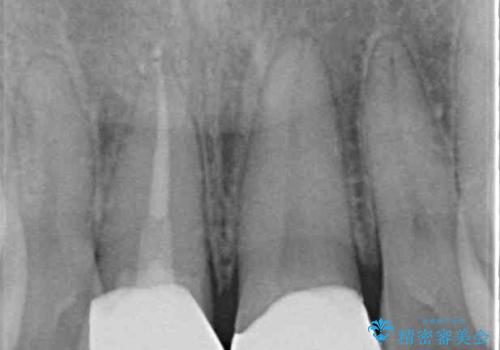

歯をぶつけてから1年後のレントゲン写真を取りましたが、どちらの歯も大きな異常は認められませんでした。

今後も定期的にレントゲン写真による経過観察が必要となります。